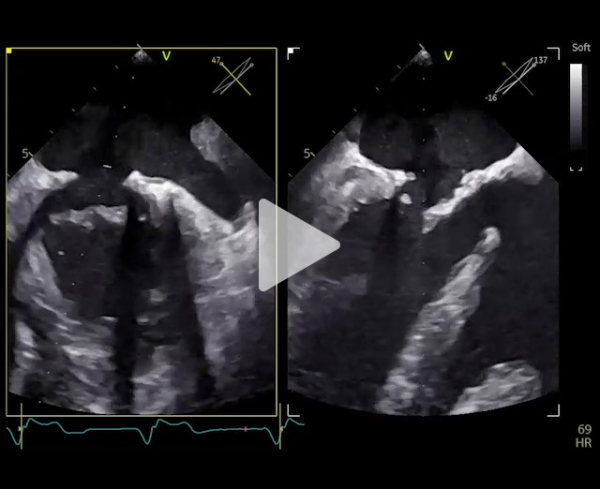

Nouvelle évaluation globale : ETT - ETO

- Ventricule gauche dilaté 87 ml/m2, FEVG 79%.

- Oreillette gauche dilatée 55 ml/m2

- Valve mitrale : plastie mitrale sur valve barloïde, insuffisance mitrale de grade 3

- Restriction au niveau de P3

- SOR 30 mm2, VR 54 ml, PISA 8 mm

- Rapport ITV 1,8, onde E 1,8 m/s

- Pas de reflux dans les VP

- Gmoy 6 mmHg

- Fonction ventriculaire droite altérée

- Forte probabilité d’HTP